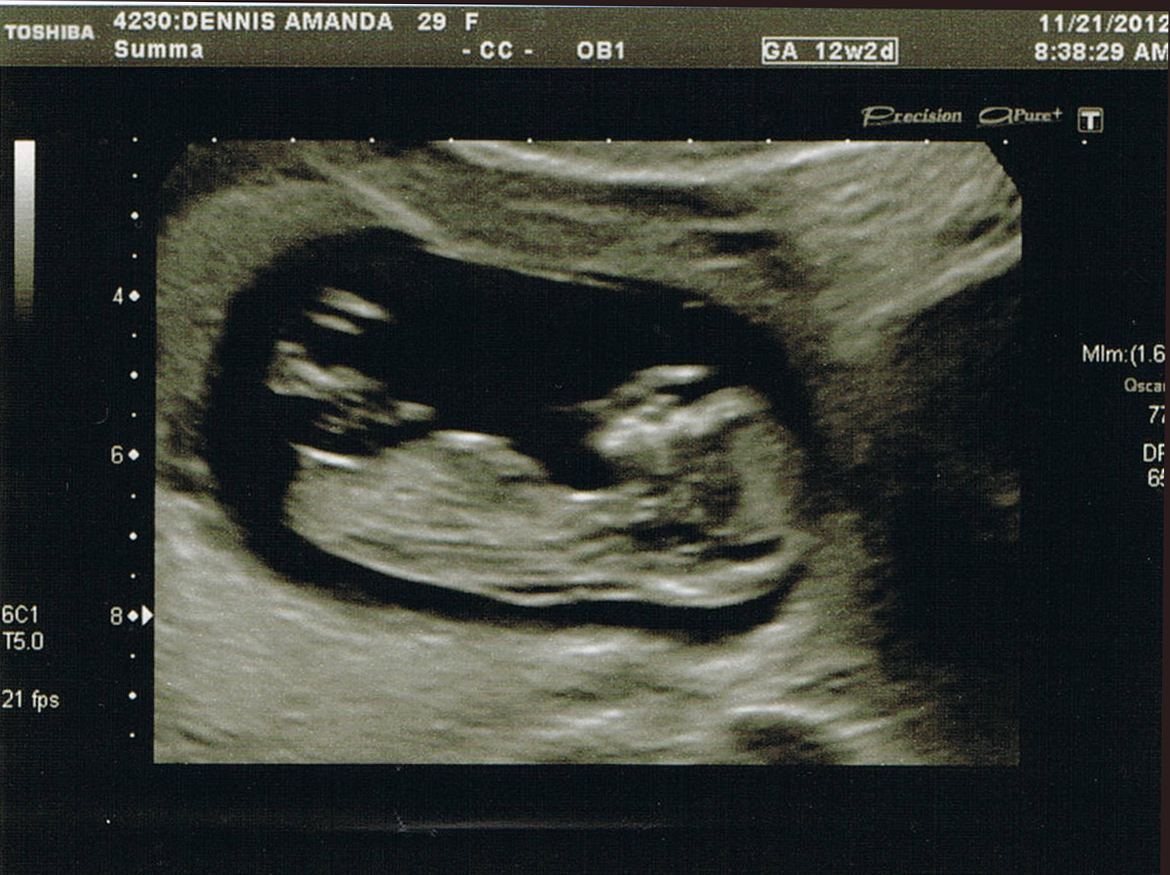

Update, 16 week ultrasound, tech was 99.9% sure it's a GIRL!!! I'm still in shock, but over the moon! Thanks everyone for all of your guesses!Attachment 7388

Im no expert but that nub looks girly to me :) x

I'd say girl from nub and skull shape

Very girly looking nub!

Girl. That nub is very flat.

Does anyone guess girl based on skull shape? Or are all of these guesses based on the nub? Just curious.